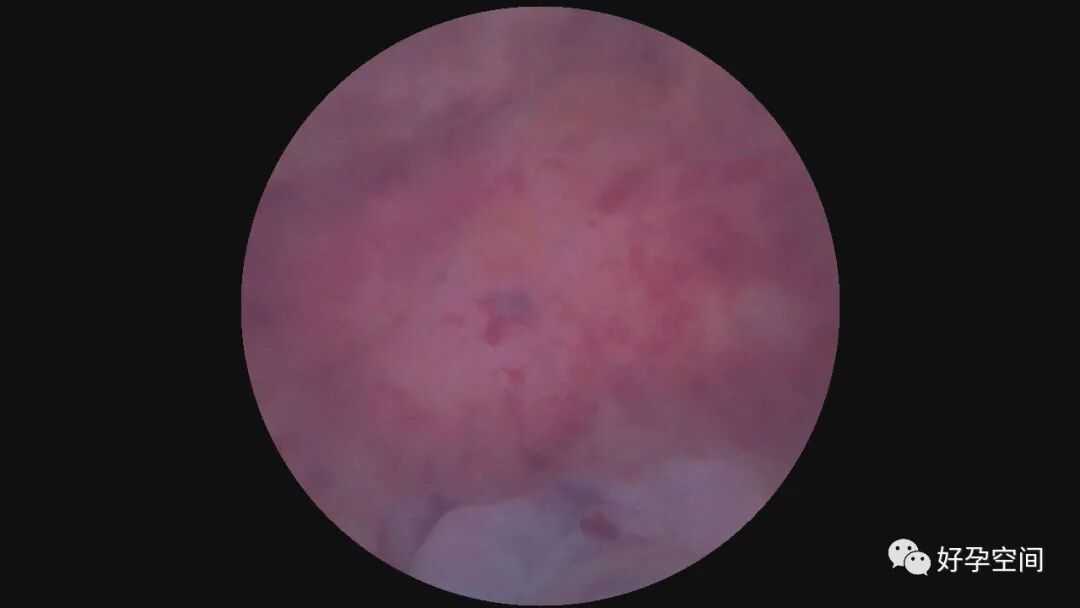

病例2:51岁,G2P1,顺产1次。安环29年,绝经1年,发现宫颈息肉1月。一次性宫腔镜见T型环嵌顿于宫腔,铜环套破碎,异物钳取出。宫颈管息肉约2.5cm*1.5cm*1.0cm,息肉根部位于宫颈管下段前壁,单级电针切除息肉。